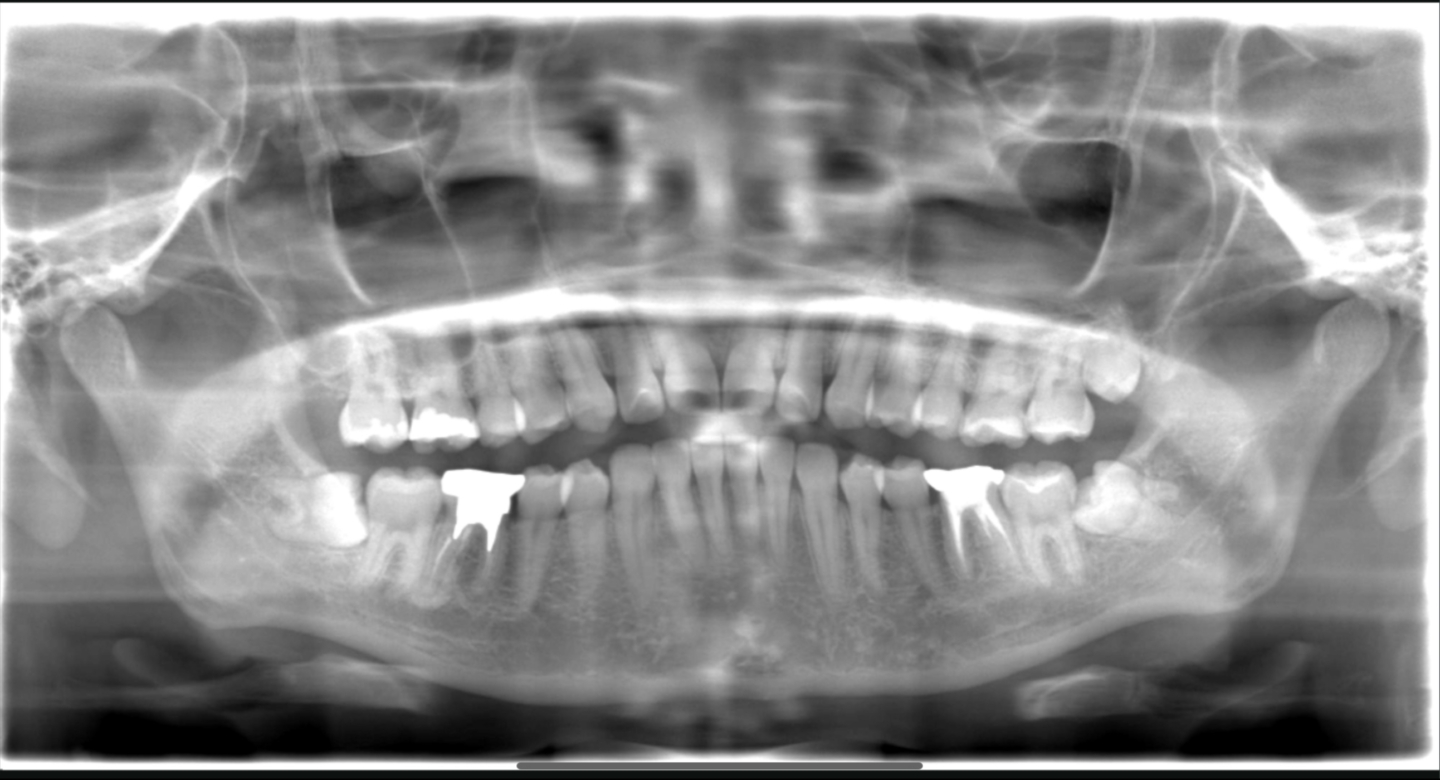

■ 2024年のパノラマ所見

2年後のパノラマでは、下顎左右とも親知らずは抜歯済みです。

抜歯部は骨で安定し、第二大臼歯周囲の環境も改善しています。